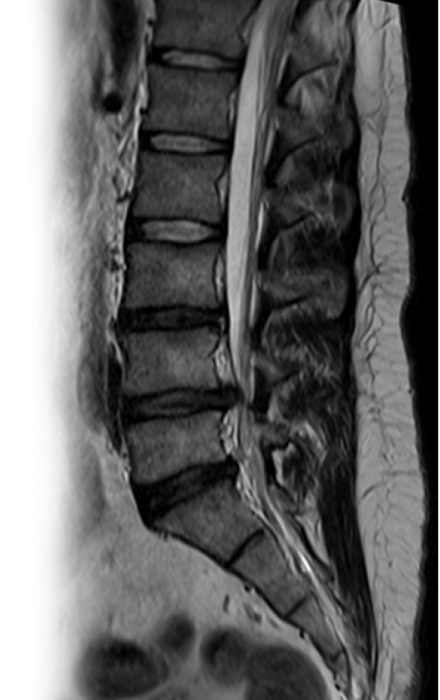

МРТ пояснично-крестцового отдела позвоночника

Магнитно-резонансная томография пояснично-крестцового отдела позвоночника – важный метод исследования, который позволяет оценить состояние пояснично-крестцового отдела позвоночника.